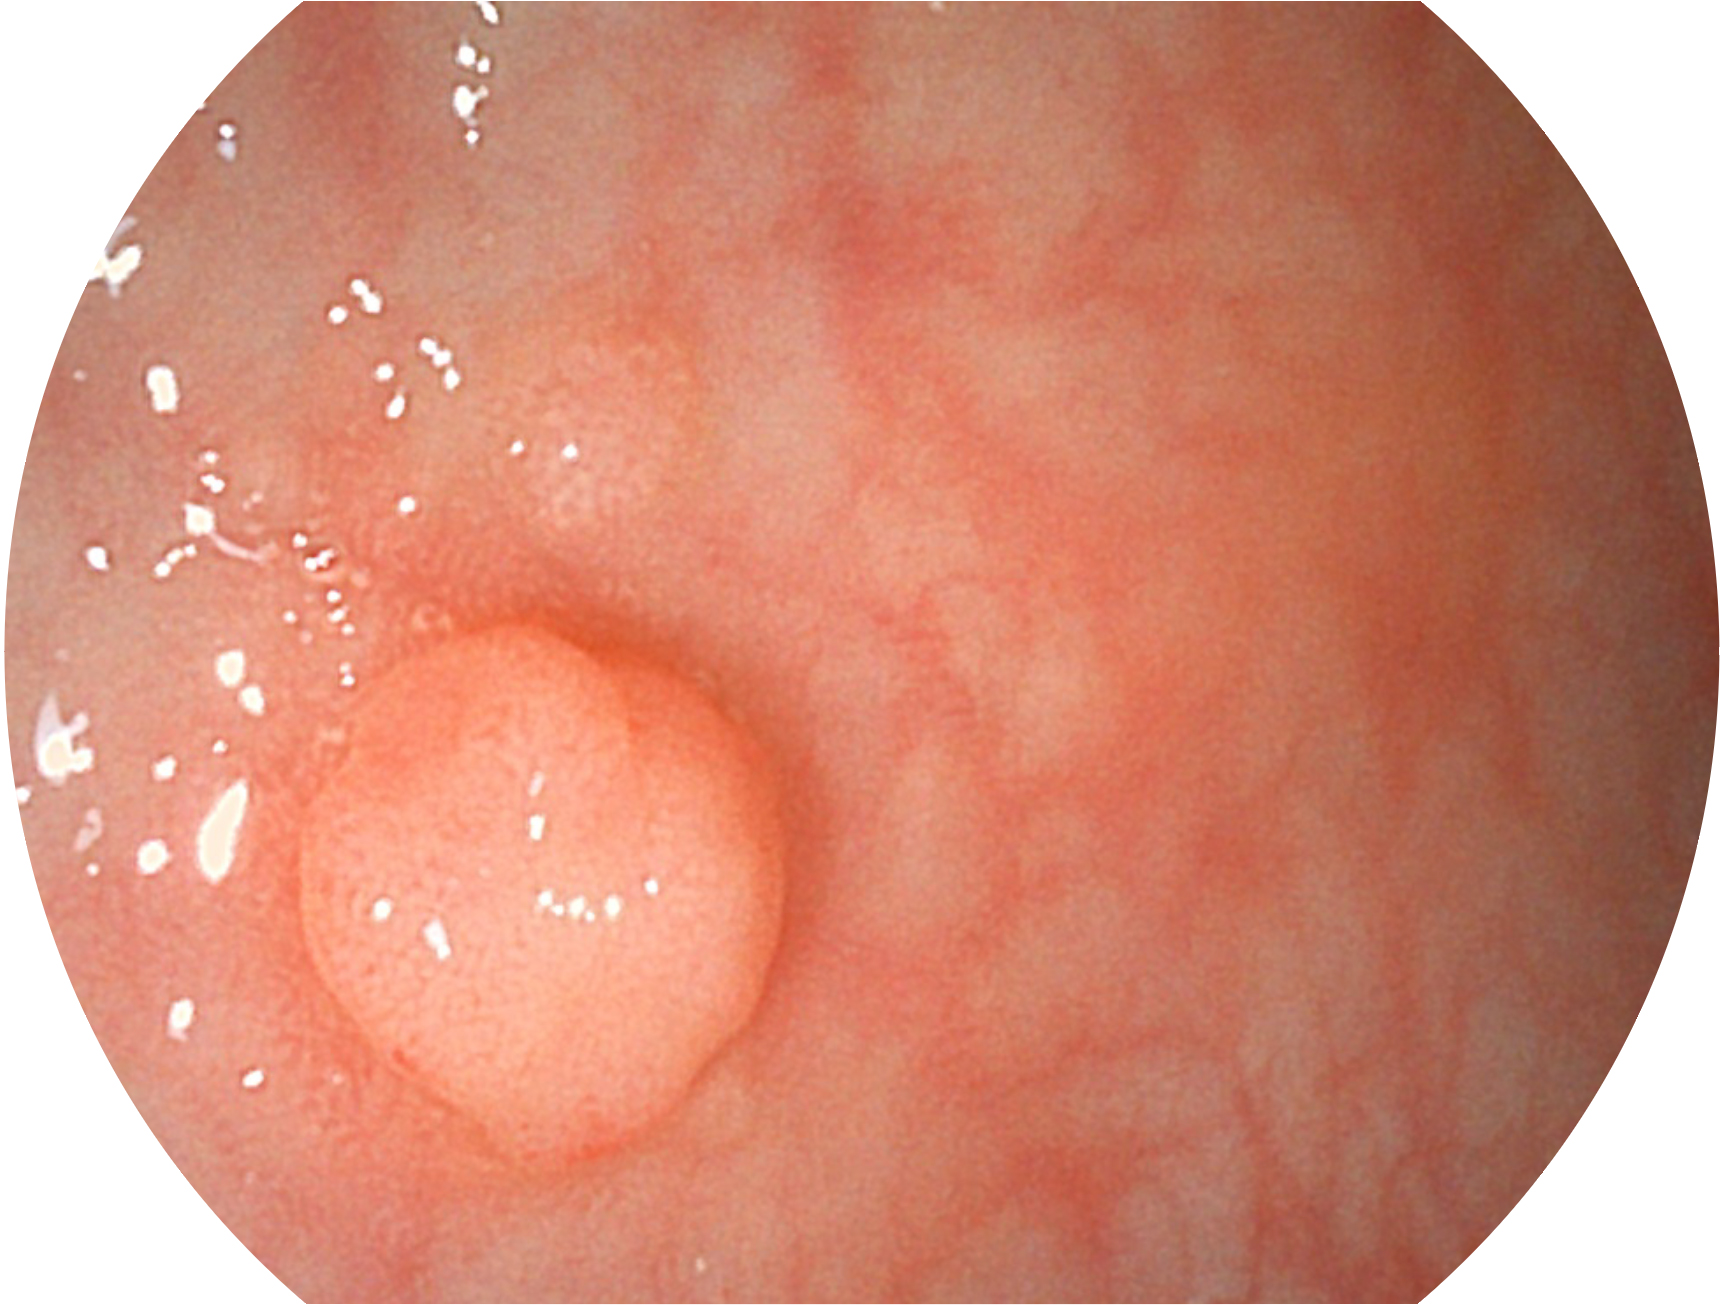

开立新开发的内镜染色技术,主要是基于多波长LED 光源的开发,VLS-55Q 四波长LED 光源是由四个不同颜色的LED光按照相应照明模式所规定的特定发光比例进行合束后形成,合束后形成的照明光的光谱由红光、绿光、蓝光及蓝紫光这四个不同的波段范围构成。具有更高光谱自由度,通过光谱比例的控制,实现了聚谱成像技术,英文全称为“Spectral Focused Imaging, SFI”,缩写为“SFI”和光电复合染色成像技术,英文全称为“Versatile Intelligent Staining Technology, VIST”,缩写为“VIST”。